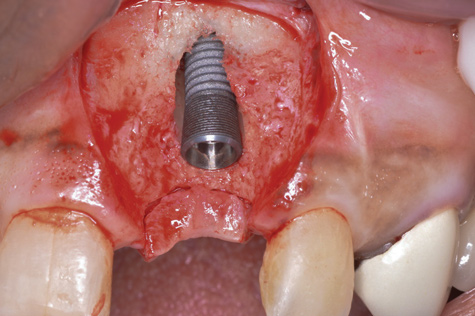

(6.) A 3.6-mm diameter implant was removed with a 4.0-mm diameter trephine drill. The apical portion of the implant was luxated carefully to preserve as much bone as possible.

Figure 6